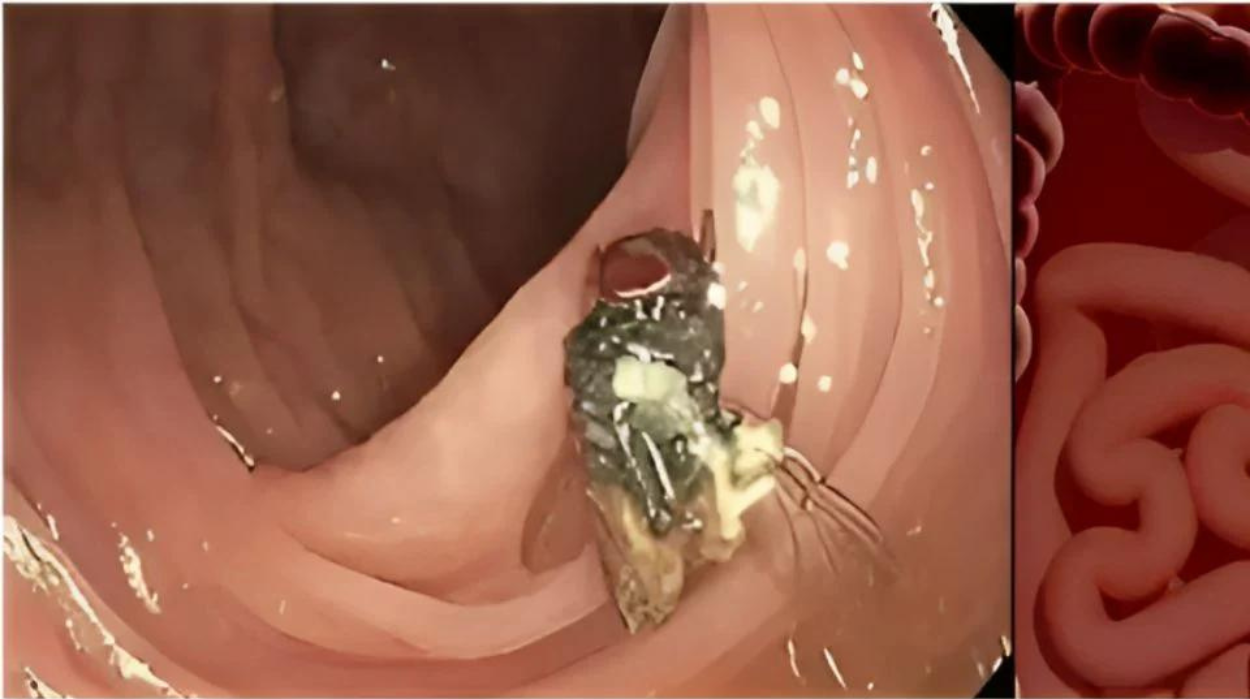

Estados Unidos.- Médicos en Missouri, Estados Unidos se vieron sorprendidos mientras realizaban una colonoscopia a un hombre de 63 años.

La persona estaba realizándose un control rutinario del cáncer cuando de pronto se percataron que había una mosca intacta en el colon del paciente, según un estudio publicado en la revista American Journal Of Gastroenterology.

"Tener una mosca tan intacta como ésta es algo inédito", declaró Matthew Bechtold, el gastroenterólogo que llevó a cabo el procedimiento.